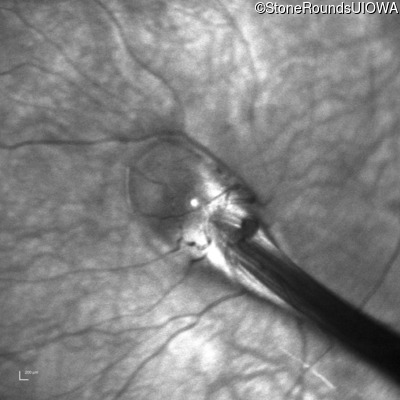

AD Familial Exudative Vitreoretinopathy (IIIE2b)

Age at visit: 23 months

This 23 month old male has had nystagmus since shortly after birth. He was born at term (7lbs 12oz).

AD Familial Exudative Vitreoretinopathy FZD4 Ser228Arg AGC>CGC   AD